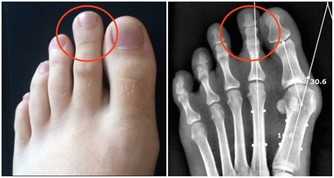

10.手腳發麻

糖尿病、痛風、老年人大腦缺血等很多原因都可以引起晨起手腳發麻,這類人應及時到醫院診治。